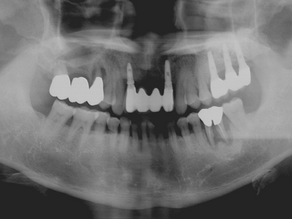

Post extractive implant in the aesthetic area

initial situation of 12 and 11 X-ray situation digital diagnostic wax 2 implant IS II Neobiotech inserted after the roots extraction...